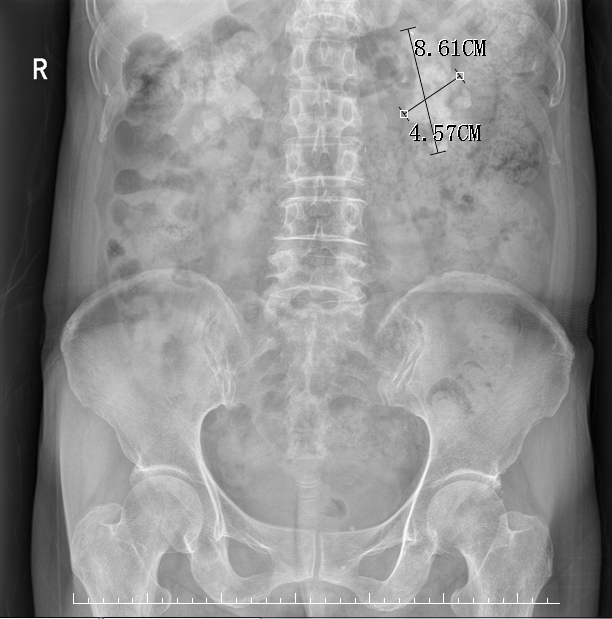

术前腹部平片

近日,娄星区人民医院(娄星区妇幼保健院)外科主任王卫东带领泌尿外科团队,顺利完成运用一次性电子输尿管软镜配合“医为特”智能控压负压吸引,无创经自然通道输尿管软镜碎石取石术治疗左肾8.61*4.57厘米完全鹿角形结石病例。

患者,阳某,女,72岁,因“双侧腰背部反复疼痛1月”慕名来到医院泌尿外科就诊,经CT检查示:双肾铸型结石,入院诊断为:1、双肾铸型结石并双肾积水 2、||型糖尿病 3、泌尿道感染。